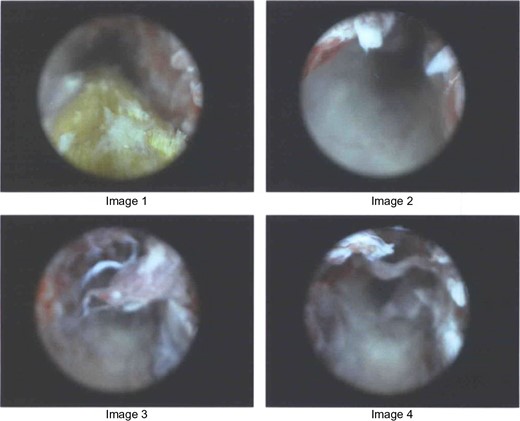

The tract was too narrow to allow a grasping instrument to open wide enough for blind retrieval. For better visualization, a cystoscope was used. The cystoscope, with water running through, expanded the tract enough to visualize the presence of a fibrous foreign body. Grasping forceps, inserted into the cystoscope, were then used to grasp and retrieve the object (Fig. 2). The wound was injected with local anesthetic and packed. The patient was put on antibiotics for two weeks due to the proximity of the tract to the contralateral femoral head with inflammatory changes present.

Images from cystoscope showing the retrieval of fibrous object.